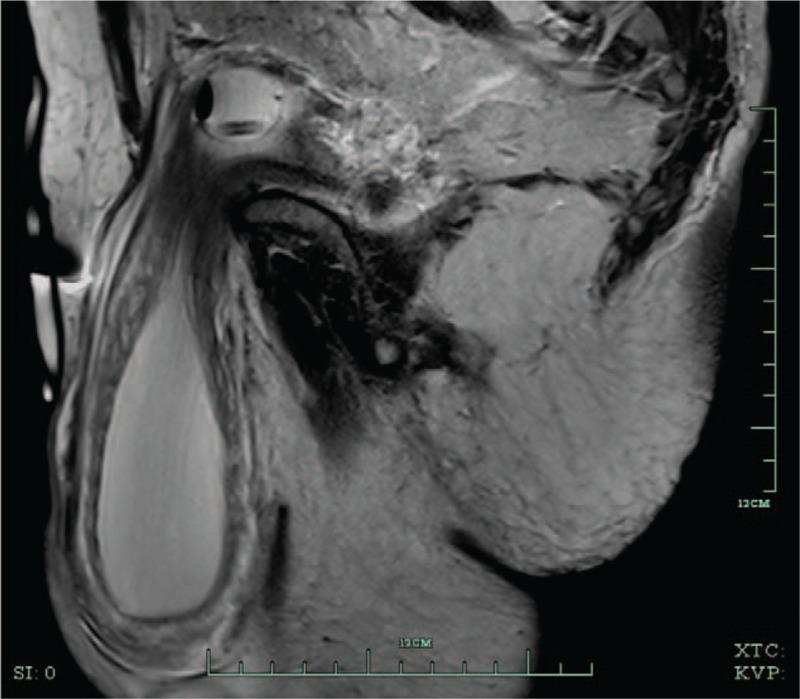

We describe and discuss the clinical findings and management of a 59-year-old man who complained of a decrease in scrotal size after voiding and 2-stage voiding requiring pressure to the scrotum.

The patient was diagnosed preoperatively as massive, bilateral, inguinoscrotal hernias, and a large, left-sided, sliding bladder hernia.